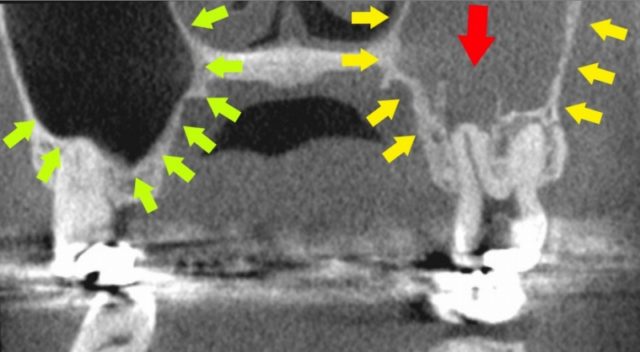

歯性上顎洞炎に なりやすい人 なりにくい人

歯性上顎洞炎になりやすい人

歯根と、上顎洞が近い人です。

上は、上顎洞内に、

大臼歯の歯根が

飛び出しています。

もし、この根が化膿すると、

上顎洞に炎症が波及しやすいでしょう。

この様な方は、

歯性上顎洞炎になりやすいと思われます。

歯性上顎洞炎になりにくい人

上は、上の大臼歯の歯根と、

上顎洞の距離がある方です。

もし、歯根が化膿しても、

炎症は、上顎洞へは、波及しにくいでしょう。

歯性上顎洞炎には、なりにくいと思われます。